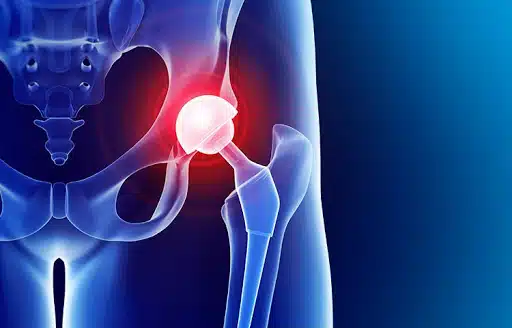

ضع في اعتبارك أنه يمكن الشعور بألم الورك في أي مكان أو حول مفصل الورك. وفي بعض الحالات ، قد لا تشعر بالألم من منطقة الورك مباشرة ، وإنما تشعر بهذا الألم من الفخذ. وتزيد فرصتك بالحصول على العلاج المناسب من خلال تشخيص نوع الألم الذي أثر على حياتك بدقة. في هذا الصدد ، سوف يساعدك الجراح باتخاذ القرار المناسب حول حاجتك إلى جراحة استبدال مفصل الورك أم لا.

يمكن أن يحصل تلف حاد لمفصل الورك في منطقة الحوض لعدة أسباب والأكثر شيوعاً هي:

- عند تمزق مفصل الفخذ وإصابته بالتهاب المفاصل أو تلفه

- ضعف الورك وكسور الحوض

- نخر وتلف عظم الفخذ بسبب ضعف تدفق الدم

- تلف الورك بسبب مرض الروماتيزم

- خلع مفصل الورك الخلقي